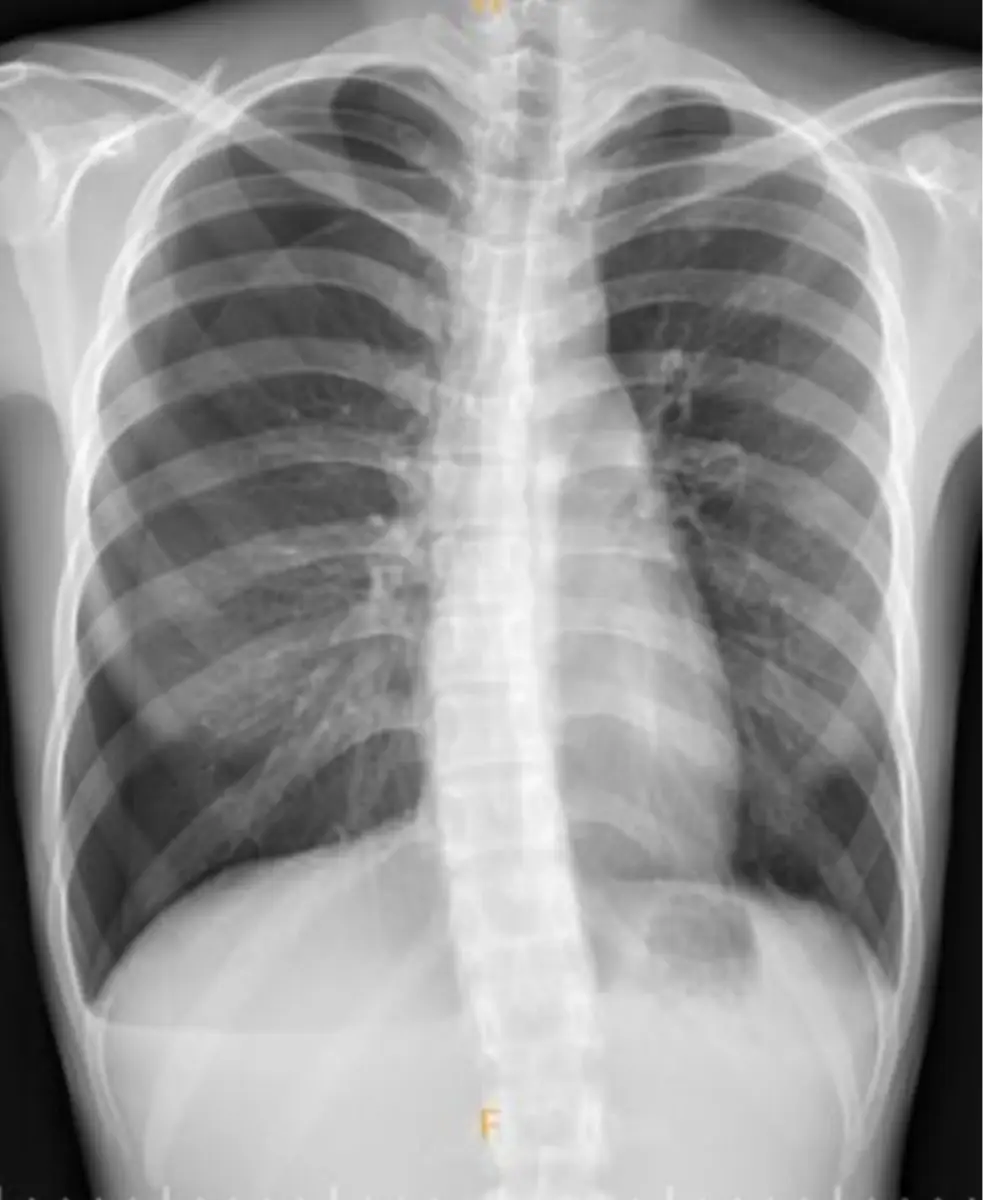

某19歲女性病患因胸悶至門診就醫。血壓 105/50 mmHg,心跳80次/分鐘。胸部X光顯示如圖。此時在門 診應優先安排下列何種檢查最為適當? 圖片描述

從正面胸部X光可見左側胸廓內有一條清晰的胸膜線(pleural line),外側無肺血管紋理,代表左側肺塌陷(spontaneous pneumothorax)。同時可見左側縱隔稍微向對側推擠,顯示可能有張力性成分,但病人目前血壓及心跳尚未顯著不穩定。右側肺野無異常陰影或肺不張情形。